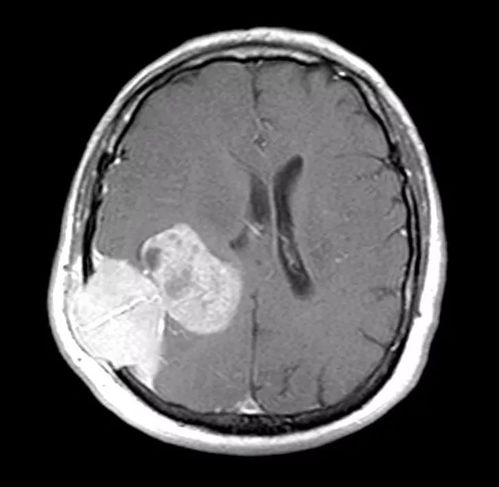

我们首先要对这些夸大其词的报道保持警惕。虽然科技进步日新月异,但目前对于癌症治疗领域的真正进展主要集中在早期检测技术上。例如,通过血液检测技术分析肿瘤DNA,可以在癌症确诊前三年就发现异常。美国约翰斯霍普金斯大学的团队已经验证了这一技术在部分癌症上的有效性。中国科研团队也在积极推进相关技术的研发,如复旦大学的肿瘤甲基化检测,能更早地发现五种常见癌症。质子刀等精准放疗技术也已经在临床上得到应用。

关于那位女博士的“创新疗法”,我们尚未看到具体的研究机构、论文发表或临床试验数据等科学证明。对于任何医疗领域的突破性成果,我们都应该保持理性看待,关注权威医学期刊或正规医疗机构发布的研究成果。目前,癌症治疗仍然需要综合手术、放疗、靶向治疗等多种手段。